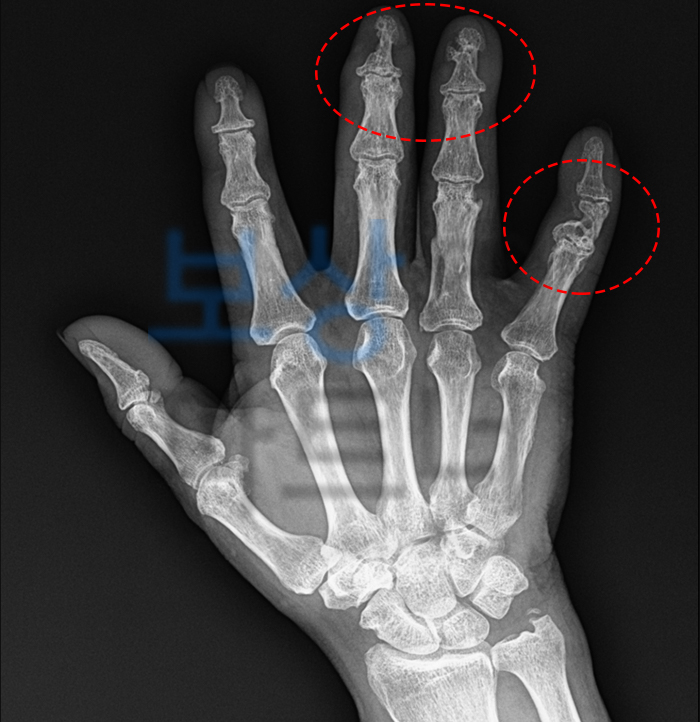

우측 3,4,5 수지 압궤상

우측 3,4,5 수지 골절

우측 5수지 건파열

이 사고로 중지, 약지, 소지가 압궤상 및 골절상을 입었으며 새끼손가락의 힘줄이 완전히 파열되었습니다. 게다가 연부 조직의 손상이 심하여 피부 이식이 필요한 상황이었습니다.